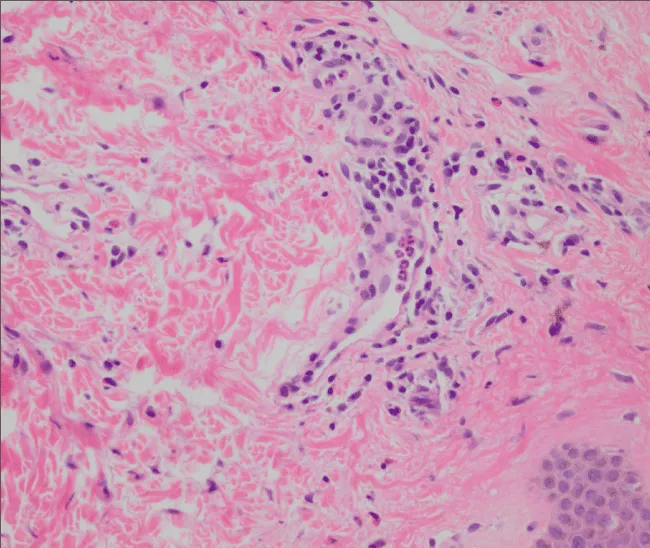

It is a prospective study was performed in dermatology departments, at Al-Azhar Univerisity Hospitals, Cairo, Egypt. The study was conducted within the period of January 1st, 2016 to March 1st, 2017. A convenience sampling method was used for selecting the cases. Any patient with urticaria for more than six weeks was included in the study. Full clinical (Figure 1) and laboratory tests were conducted to exclude those patients with any finding which may be a cause of the urticaria. For the controls, an equal number of persons was chosen and matched by age and gender with cases and free from features of urticaria, gastrointestinal symptoms and any other condition in which H. Pylori may exist. As a result, 100 persons were identified for the cases and 100 for the controls as a sample size for the current study. The followings patients were excluded from the study; patients suffered from physical urticaria, patients consuming proton pump inhibitor within two weeks, antibiotic and Bismuth within four weeks preceded enrolling in the study. The data was collected through direct interview and clinical examination of the patients and controls, in addition to the results of the laboratory findings. The purpose of the study was explained for each participant and verbal consent was obtained from them before inclusion in the study, and anyone wasn’t interested to be involved the study was excluded. An anonymous questionnaire form was prepared to collect data, and filled by the researcher through direct interview. The questionnaire was composed of two parts; the first part was composed of data about socio-demographic characteristics of the study sample e.g. age, sex, residency, marital status, educational level and occupation, while the second part was composed of data about history, clinical and laboratory findings from the study sample. The following laboratory investigations were applied to all the participants in the study: complete blood count (hemoglobin, white blood cells, differential count), erythrocyte sedimentation rate, thyroid function test, hepatitis B virus, hepatitis C virus, general urine examination, general stool examination and H. pylori antigen detection in stool by enzyme linking immunosorbent assay (ELISA) test. H. Pylori antigen Enzyme Immunoassay test (EIA) KIT was used for detection of H. Pylori antigen in the stool sample with specificity 98% and sensitivity 95% of the test [20]. The H. Pylori Antigen EIA test Kit is a solid phase EIA based on sandwich principle for the qualitative and quantitative detection of H. Pylori antigen in stool [20]. Also, Skin biopsy was done for every patient with 5 ml punch biopsy under local anaethesia and histopathological asseseement was done (Figures 2,3). In addition, gastric endoscope and gastric biopsys were done in addition to histopathological assessment by H&E and Geimsa stain for detection of Helicobacter Pylori (Figures 4-6). Endoscope was done for patient who was positive stool antigen test.